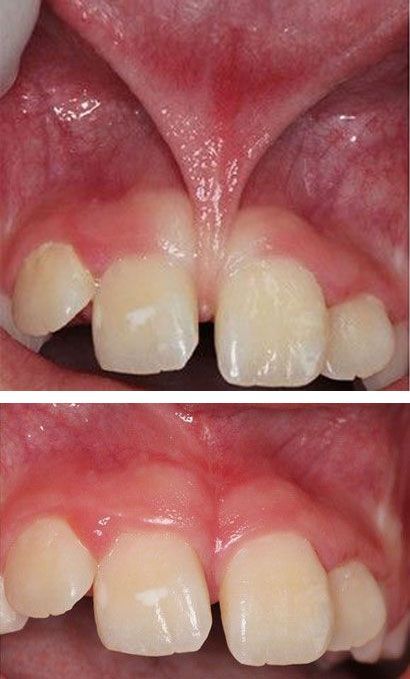

Frenillo labial superior corto

Su aparición en niños es causada debido a el hueco que se produce entre dos dientes, también denominado diastema. Si el infante tuvo problemas en la lactancia provocados por este frenillo, es probable que se presenten también problemas dentales, por lo que se sugiere rutinas efectivas de higiene para prevenir la acumulación de bacterias en la zona.

Como tratamiento se sugiere realizar una frenectomía, la cual es una operación sencilla y poco invasiva con anestesia local. Como acompañamiento a este procedimiento, se sugiere la ortodoncia para corregir el hueco entre los dientes causado por el frenillo.